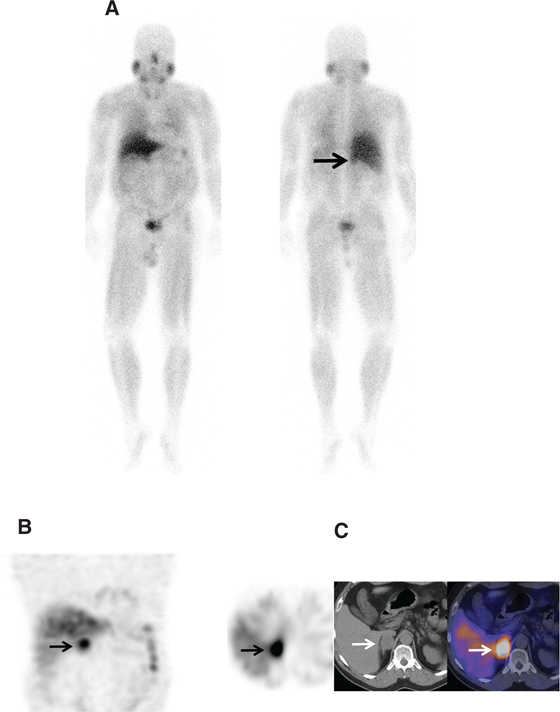

Fig 8

Figure 8 A 60-year-old woman with familial paraganglioma/pheochromocytoma syndrome status after right adrenalectomy with increased plasma metanephrine levels. (A) Previous whole body planar I-123 MIBG scan with attenuation-corrected SPECT, CT, and fused SPECT/CT images show increased uptake in multiple osseous lesions (white arrows). The patient was subsequently treated with I-131 MIBG therapy. (B) Ga-68 DOTATATE PET/CT maximum intensity projection (MIP) image of the skull vertex to the proximal thigh performed 5 years post-therapy because of increasing tumor markers shows widespread somatostatin receptor-positive bone metastatic disease with marked tracer uptake (arrows). (C) An F18-FDG PET/CT performed 1 week prior showed minimal to no uptake in corresponding osseous lesions.